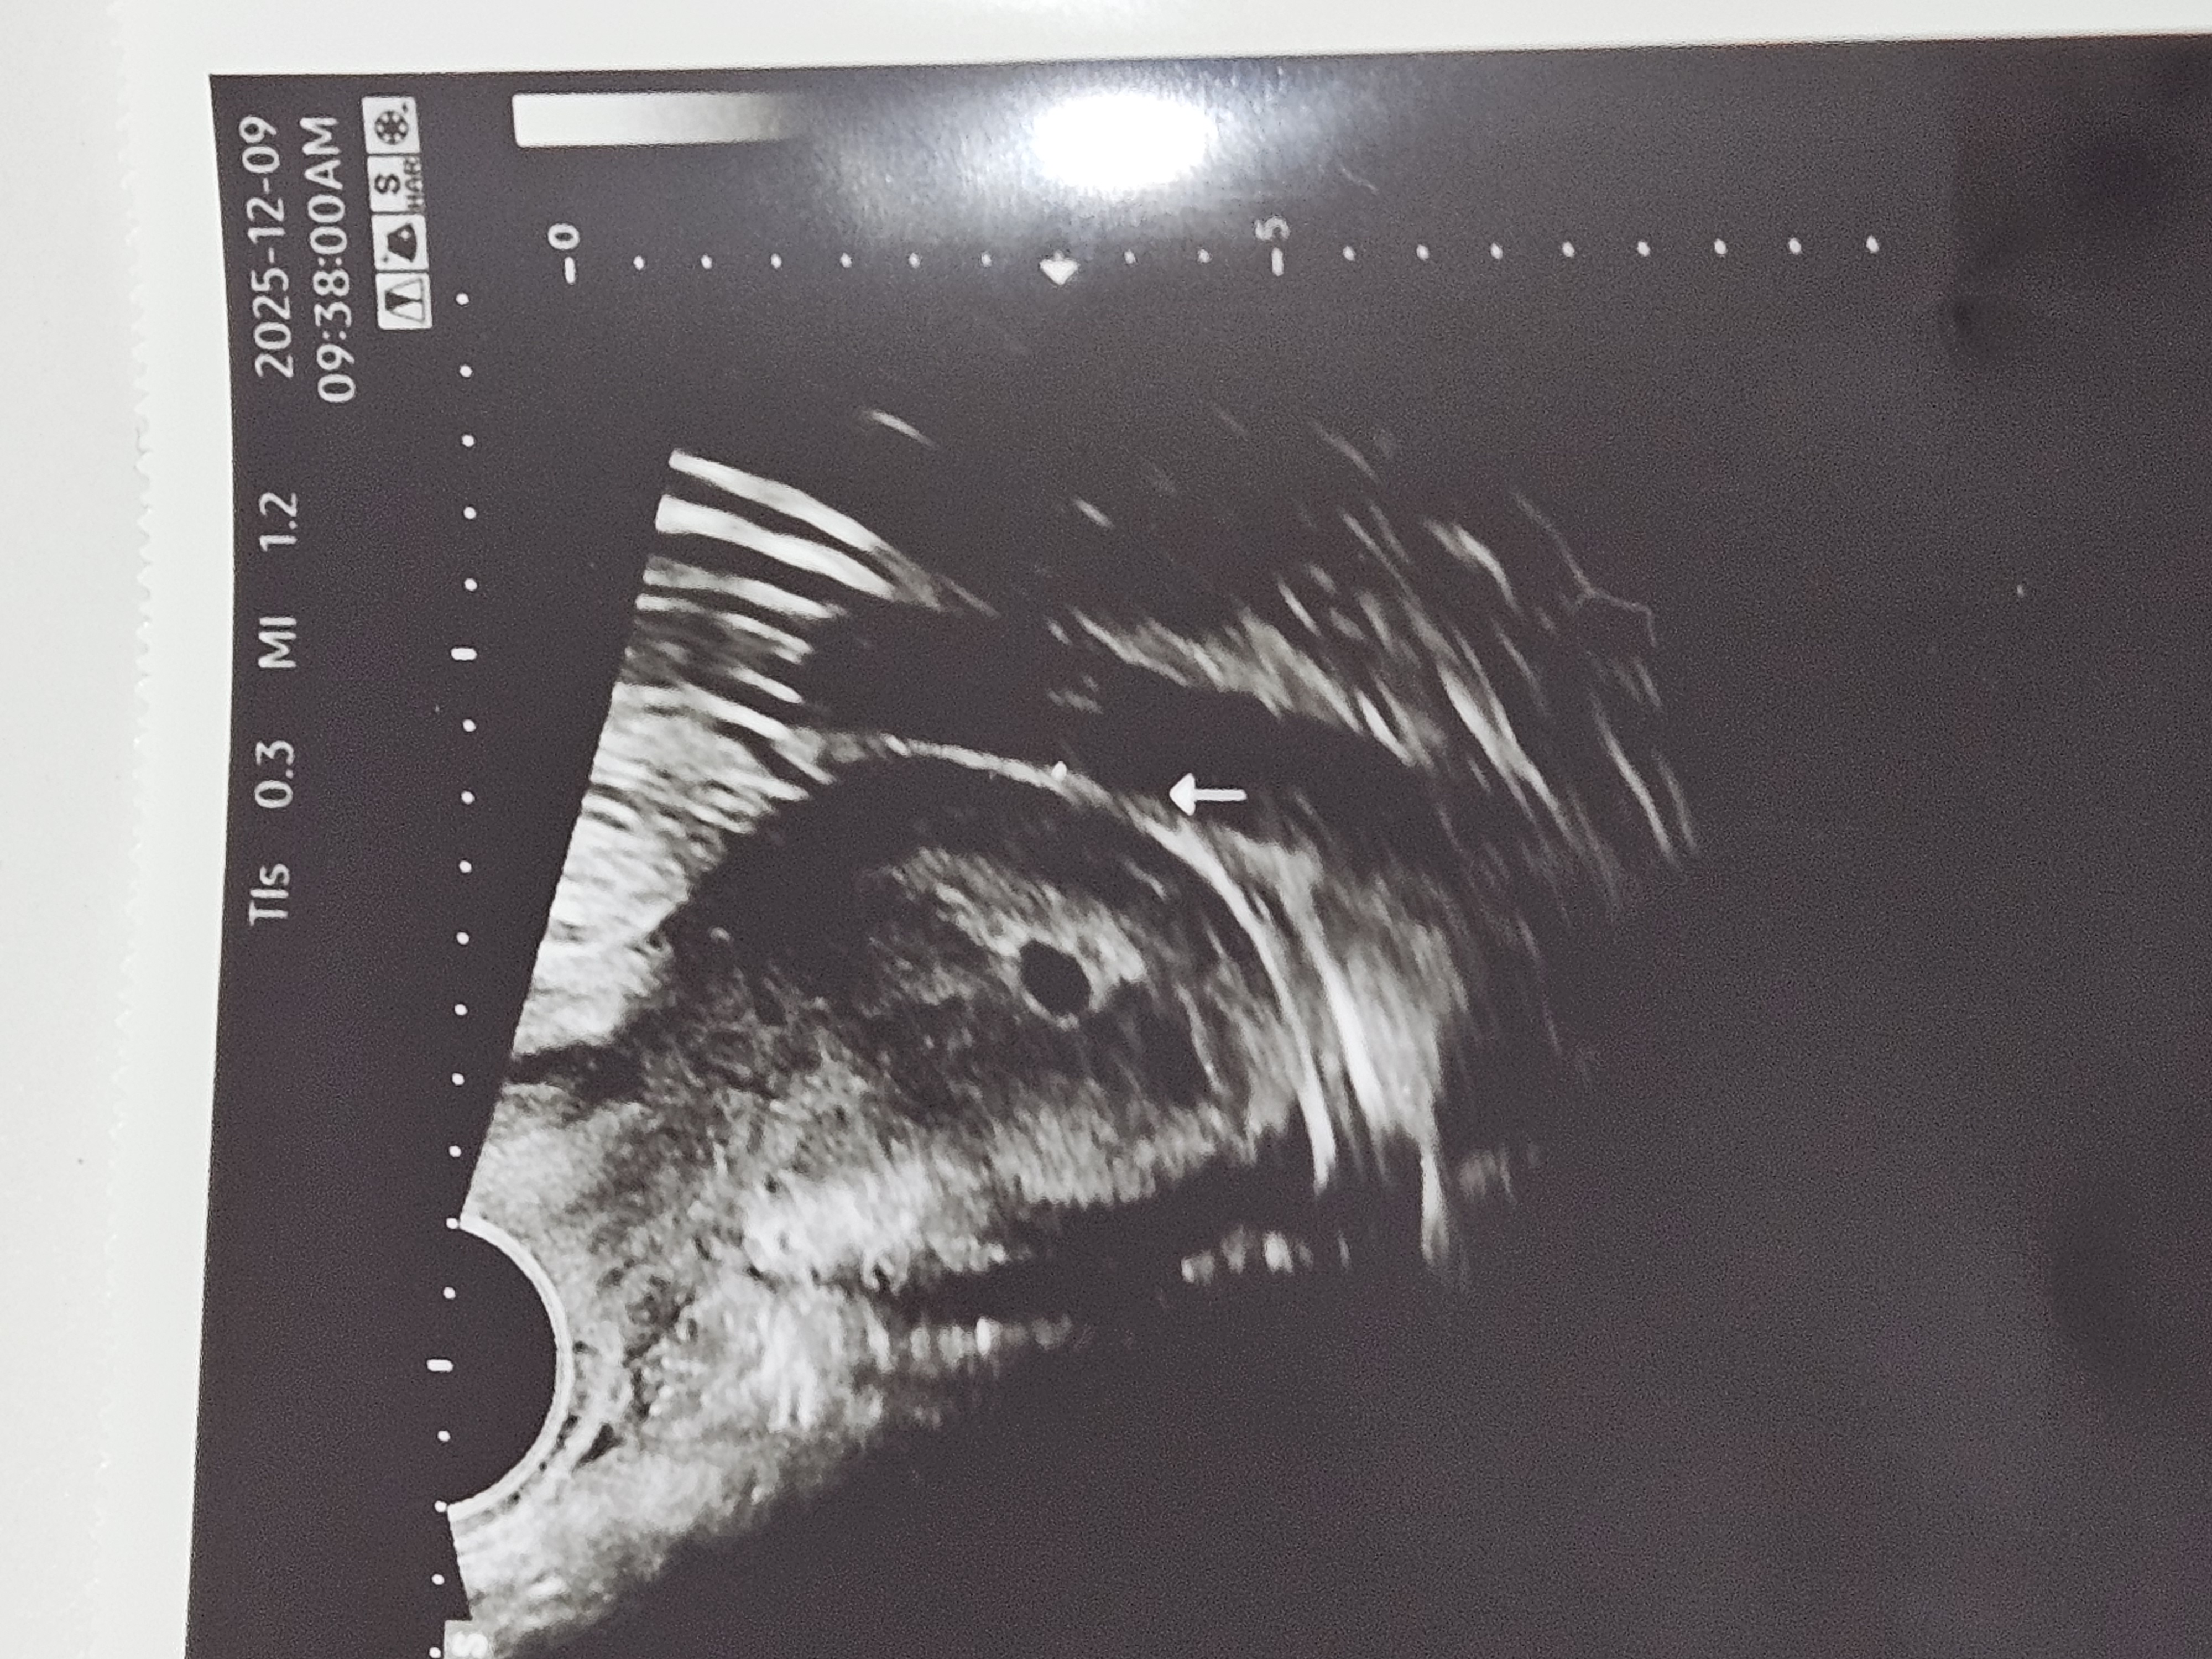

쌍둥이일까요?

4주 2일(배란 19일차)입니당 16일차에 역전해서 처음 아기집 보고왔는데 위에는 아기집이 확실한데 밑에는 아기집인지 피고임인지 모르겠다고 담주에 한번 더 오라고 하시더라구용.. 원래 보던 원장님이 안계셔서 다른 분한테 본거라 이번주에 한번 더 가볼까 싶은데 어떻게 보이세여?? 피검은 12일차 122, 15일차 704였어요!

네넵 어제 애기집+난황보고왔는데 단태아였어영 ㅎㅎ